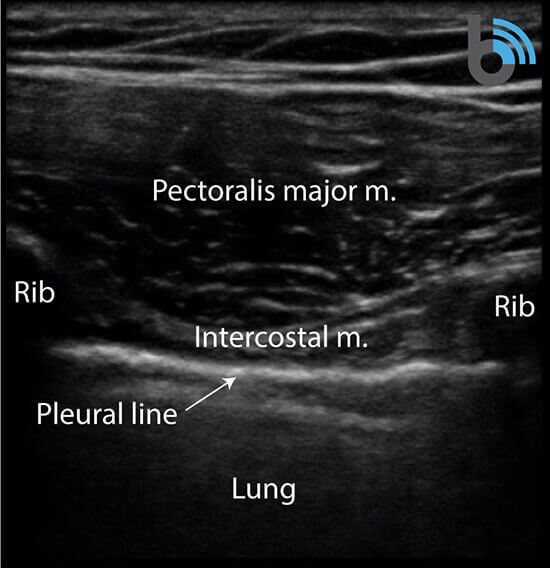

Anatomy

- The ribs will appear as convex hyperechoic lines with acoustic shadows.

- Located between the ribs are the hypoechoic intercostal muscles and the smooth, thin hyperechoic pleural line.

- These structures form the “bat sign”: the shadow of the ribs form the wings, while the area between the ribs represents the body.

Lung Sliding

- The pleural line is comprised of the parietal and visceral pleura, but will appear as a single, thin hyperechoic line.